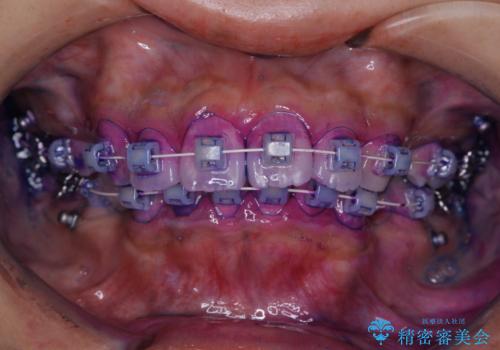

ワイヤー矯正を初めてから2カ月 歯磨き指導とPMTC

- ワイヤー矯正が開始して2カ月が経過しました。まだなかなか歯磨きが上手に出来ないのため、クリーニンングを希望されました。PMTC30分コースと歯磨き指導を行いました。

ワイヤー矯正中はブラッシングが難しくなるため、磨き残しが多くなることがあります。適切な道具を使って、適切なブラッシング方法を習得することで、磨き残しを減らすことができます。

また、矯正で歯の移動があると今までなかったところに隙間が出てきたり、ガタつきが解消されてきたりすることで、お口の中の環境が変わります。